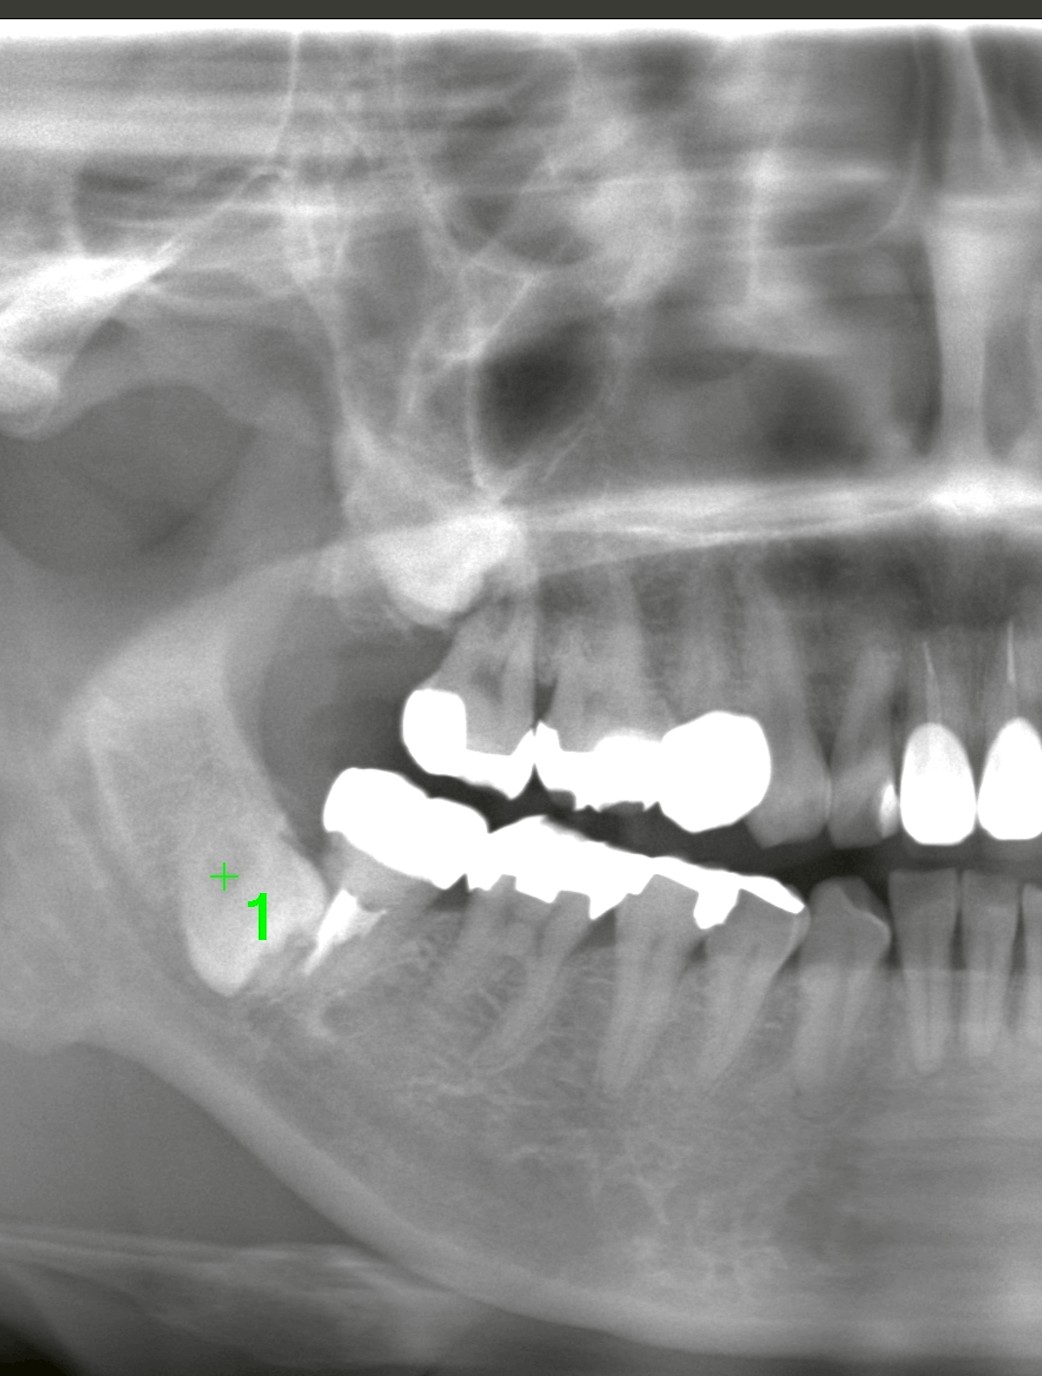

最終的な判断はレントゲン・CTで行います

親知らずの判断には

* パノラマレントゲン

* CT(立体画像)

が非常に重要です。

特に

* 下歯槽神経との距離

* 上顎洞との位置関係

* 歯根の形態

などを正確に把握することで、安全性を考慮した治療方針を決定します。